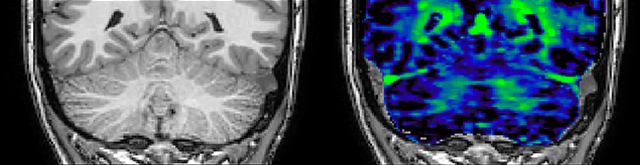

He says the accelerated scanning is achieved via the use of Compressed SENSE and MultiBand SENSE. “We can use Compressed SENSE acceleration factors of about 10 on a 3D FLAIR for instance, which is quite remarkable compared with what we saw with the Achieva. With 3D FLAIR, we can push the spatial resolution to 0.3 cubic mm and it works. Previously, our 3D FLAIR scans lasted about 8 minutes, but now with Elition they are five minutes. The SNR is also visibly better. Our SWI and QSM scans look fantastic. Also, since a lot of neuroimaging is EPI based, using the MultiBand SENSE technique can increase temporal resolution and make it possible to run complicated DTI scans relatively quickly.”

QSM based on a Compressed SENSE multi-echo SWI.